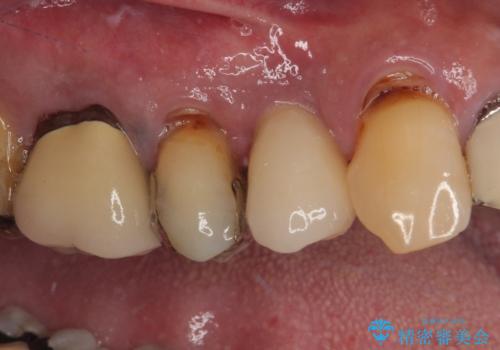

当院での根管治療および歯周外科治療を併用した保存療法、並びに1DAYインプラントによる短期間インプラント治療の双方をご説明し、即日でインプラント治療を選択されました。

仮歯を用意した上で、抜歯即時埋入・即時荷重インプラントによる補綴治療を行うこととしました。

従来のインプラント治療について回った3回の外科手術や半年移動の治療期間とは無縁の、短期間治療を達成することができました。